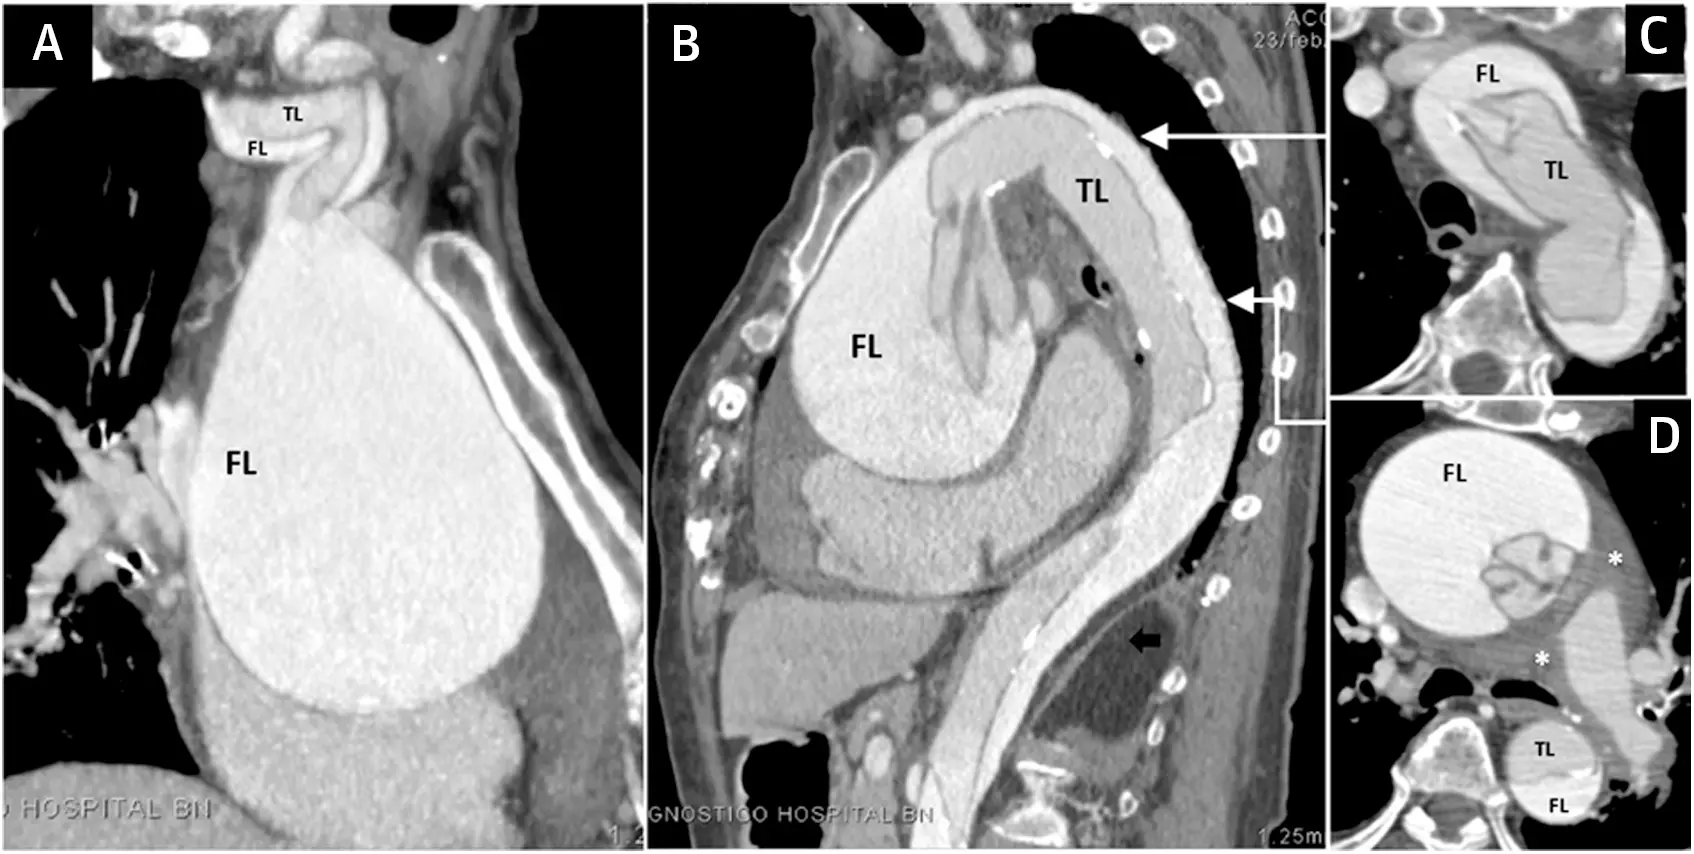

Figure caption: Type A classic dissection in a patient with an ascending aortic aneurysm. (A) Coronal computed tomography (CT) image showing involvement of the innominate artery by the dissection flap. (B) Sagittal CT angiogram shows avulsion and intussusception of the dissection flap into the distal ascending aorta and aortic arch. Axial CT images at the level of (C) the aortic arch and (D) the left pulmonary artery. Notice a pulmonary artery adventitial hematoma (asterisk) compressing the pulmonary arteries in D. FL = false lumen; TL = true lumen.1